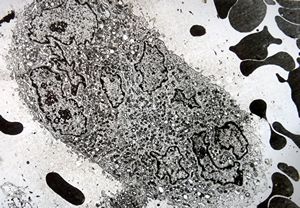

F,25y. | giant multinuclear osteoclast - aneurysmatic cyst - tibia